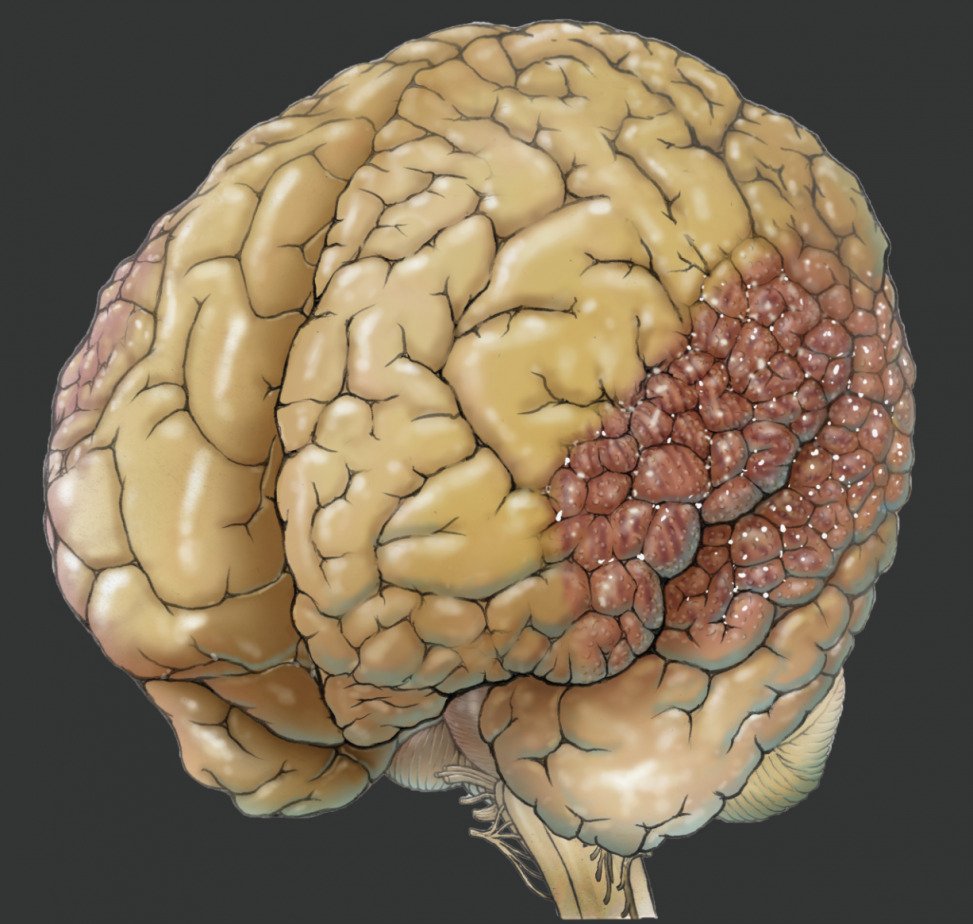

Cerebral diseases

Cerebral diseases 104 фото